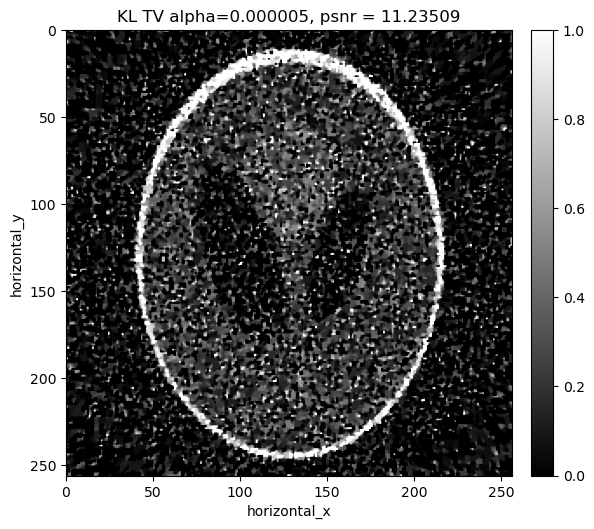

Reconstructing the noisy data using KL divergence with TV regularisation#

As in the least squares and weighted least squares case, we add in a TV regularisation term and search for an optimal regularisation parameter.

../../_images/demos_LS_WLS_KL_TotalVariation_47_0.png

../../_images/demos_LS_WLS_KL_TotalVariation_47_1.png

alpha=0.000005, psnr= 11.235